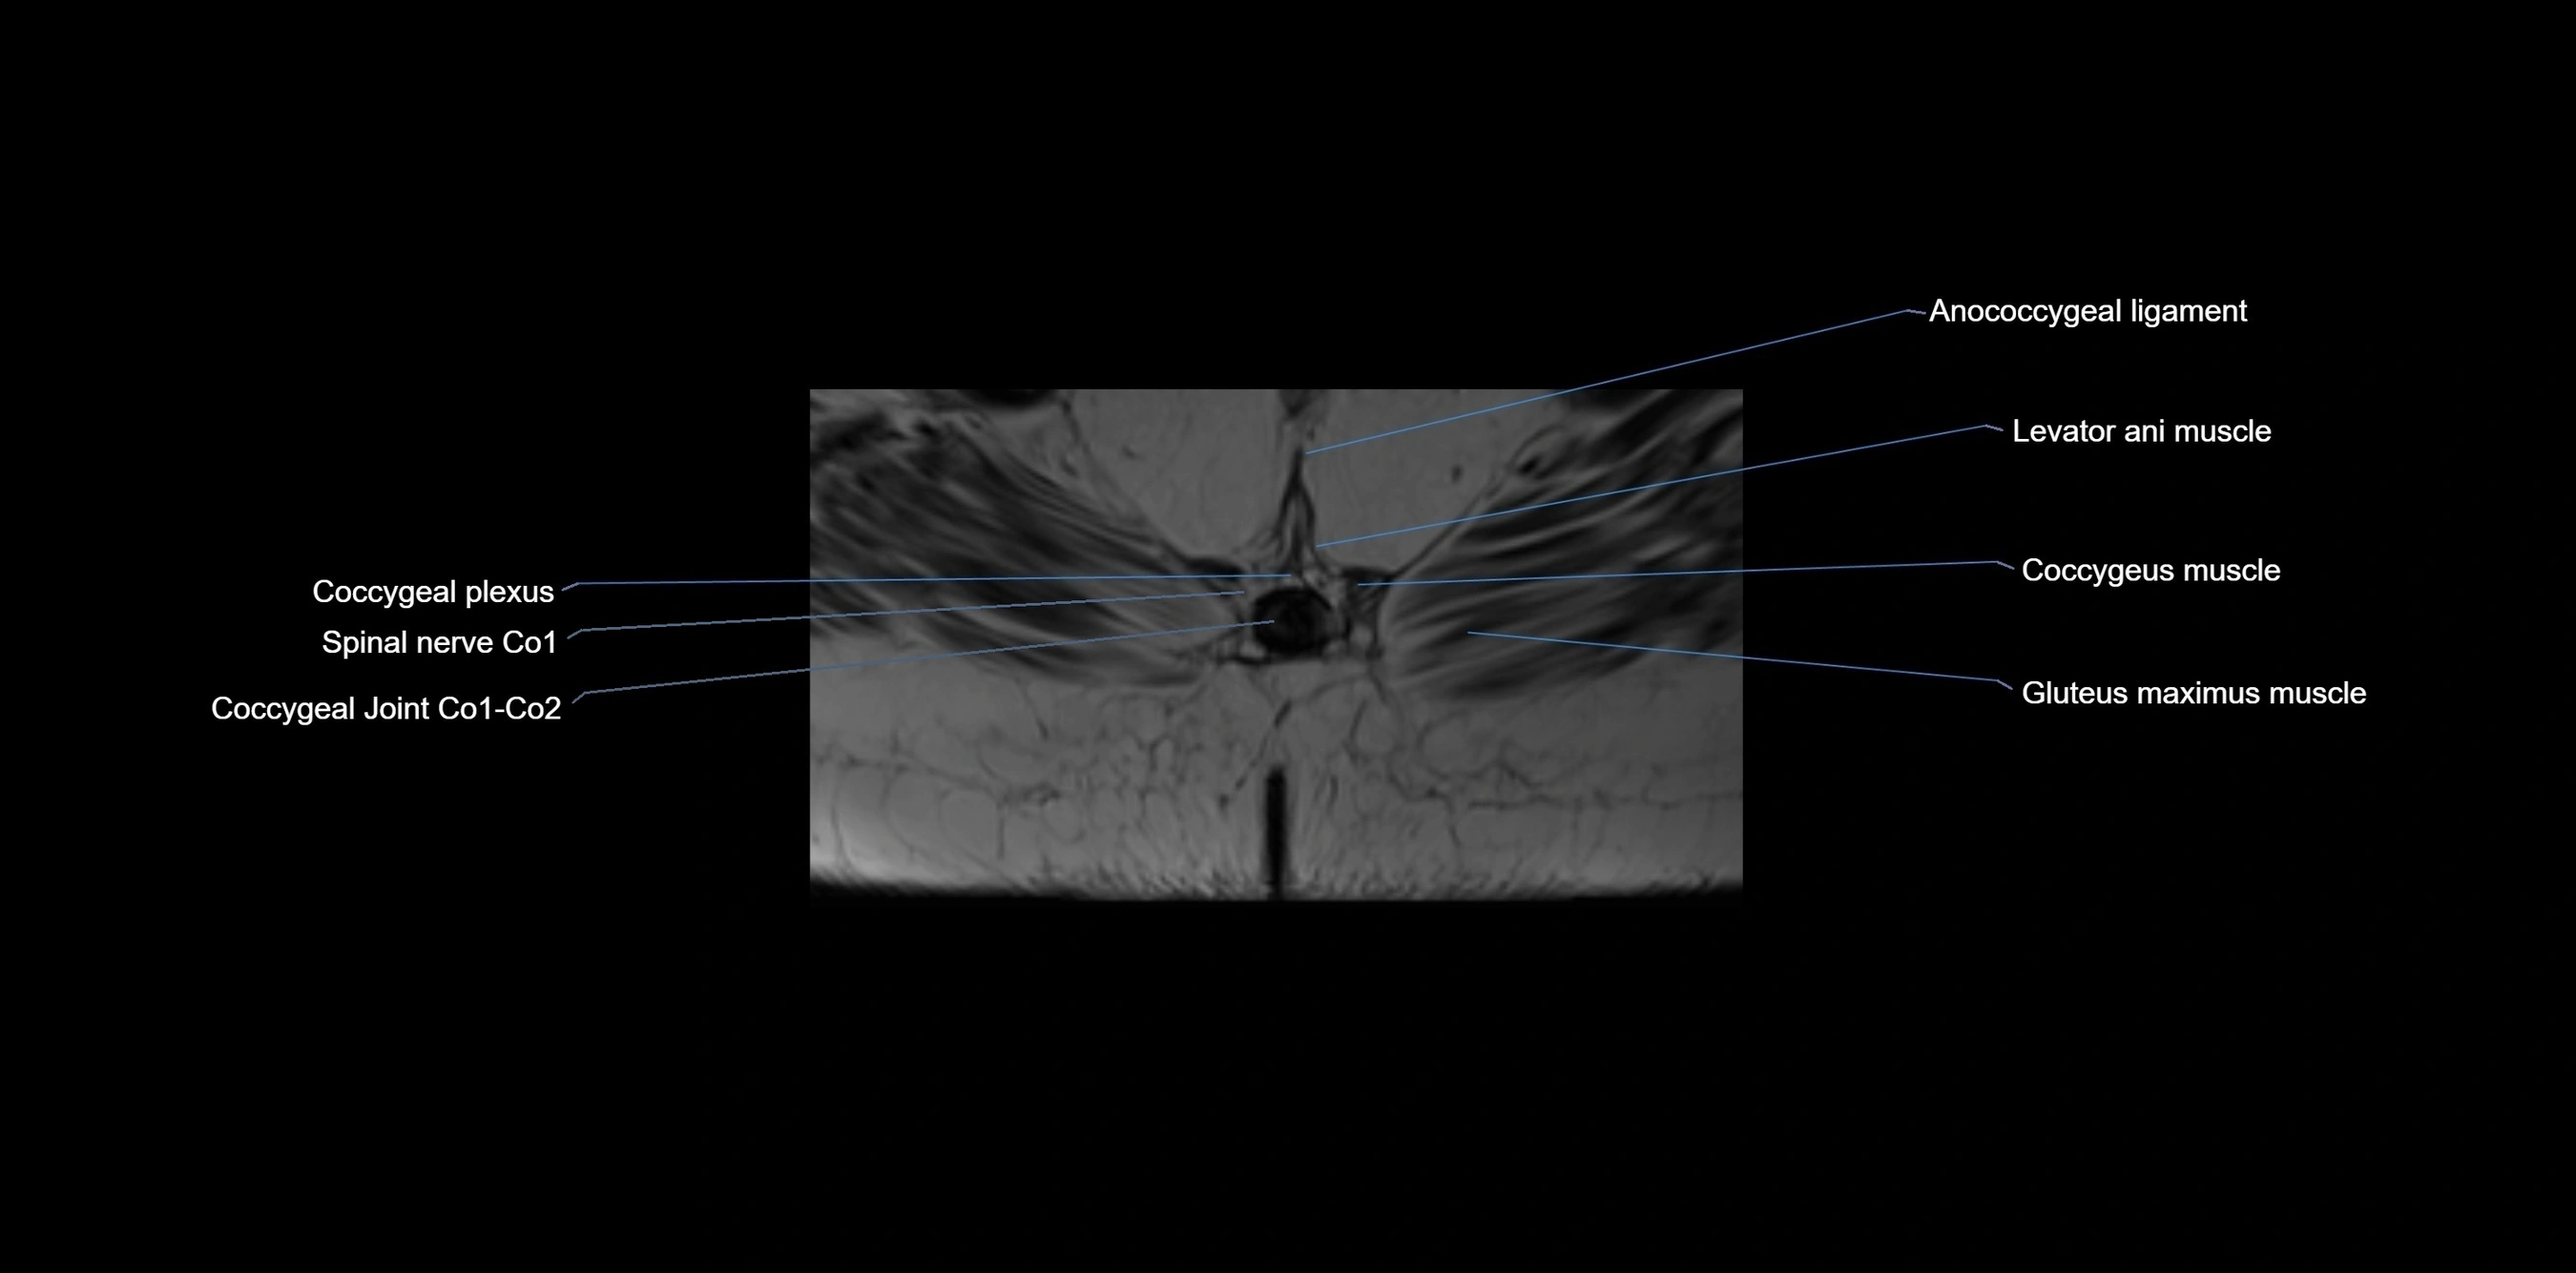

MRI image

image